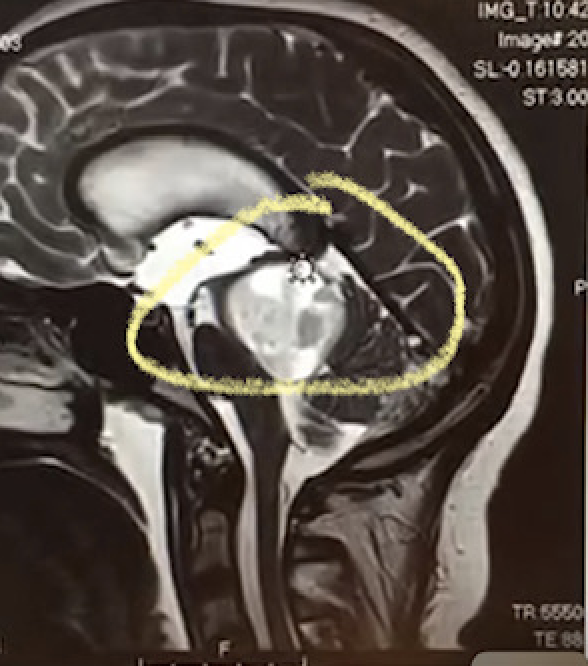

The idea of Reagan's Rainbows of Hope started after Reagan was diagnosed with a tumor, located on her brain stem, last summer. The tumor caused Reagan to feel constant nausea and headaches.

When Reagan received the first diagnosis, she was originally told the tumor would be inoperable. From there, she underwent chemotherapy to try and help treat the tumor.

Reagan underwent a successful procedure in November 2022, as doctors removed all of the tumor from her brain stem. The next step was rehab.